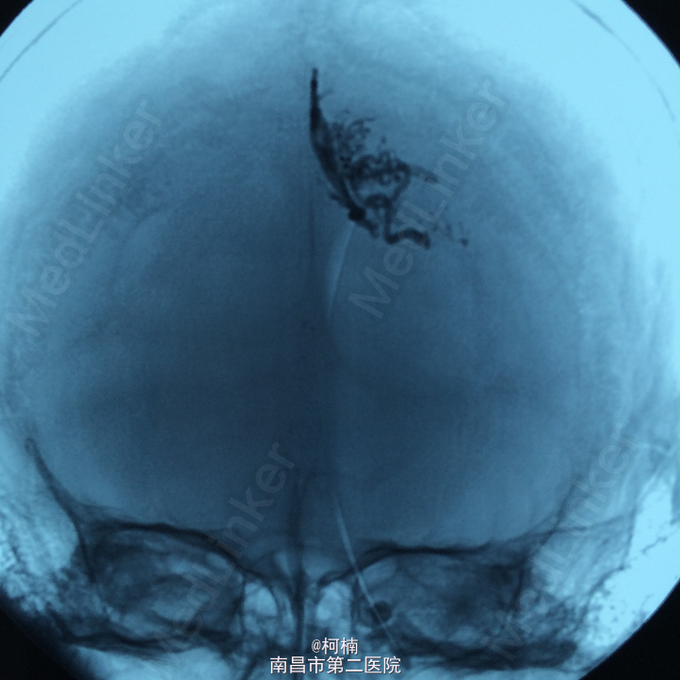

诊断:脑动静脉畸形 处理:予急诊行DSA检查,提示脑动静脉畸形,予行血管内栓栓塞治疗

随访:患者术后恢复良好。 讨论:关于脑动静脉畸形的治疗,有:1.手术治疗,现多采用显微神经外科技术切除病变血管团,单纯结扎供血动脉易复发,现已不主张采用。合并颅内血肿者须紧急手术,可能时同时切除病变。2.血管内栓塞治疗,对病变深在,位于重要功能区或高血流病变,宜行栓塞治疗。单纯栓塞治疗只能治愈一小部分病变,可在部分栓塞后再行显微手术切除。3.立体定向放射外科治疗,即X刀或γ刀,无创伤,但价格昂贵,显效慢,适用于深部直径小于3cm病变或手术与栓塞后残余病变。